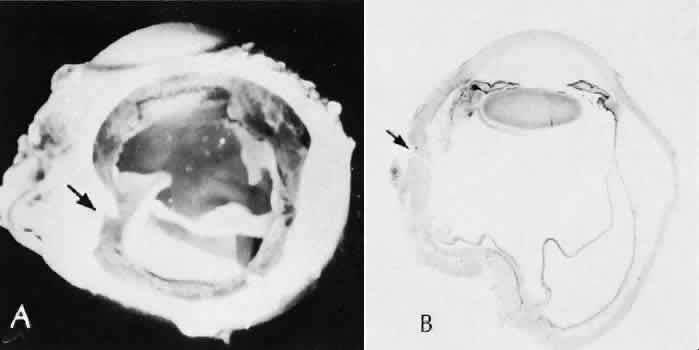

Fig. 41. Two cases of Soemmerring's ring cataract (retained lens cortex and capsule). A. Extensive opaque, well-delineated material is present in a ring-shaped configuration following a partially successful cataract extraction. The opacity is delimited by the remaining lens capsule and is located primarily in the region of the lens equator. B. The eye was examined at autopsy. The reaction is limited to the posterior chamber and within the lens capsule. Surrounding lens zonules and ciliary epithelium are not affected. C. Lens cortical material is retained in the equatorial area of the lens. This area is the least surgically accessible during cataract extraction and contains the tissue most likely to be left behind. This area also contains the cells with the greatest ability to react to trauma by undergoing fibrous metaplasia. The process is identical to anterior subcapsular cataract formation stimulated by anterior chamber inflammation. (Hematoxylin-eosin stain; × 6.) D. Residual lens cortical material ® can be clearly identified entrapped by residual lens capsule. The reaction in the lens may change the adhesive nature of the remaining anterior lens capsule. Posterior anterior synechia may form in these areas. (Hematoxylin-eosin stain; × 16.) E. In another case of retained lens material, the tissue change is less extensive and more translucent, resulting in pearl-like structures (Elschnig's pearls). The process producing this change is the same as the one in Soemmerring's ring formation, but the reaction is less extensive. Pearls are formed by aberrant attempts by lens cells to form new lens fibers. (Hematoxylin-eosin stain; × 69.)

Soemmerring's ring cataract results from the loss of anterior and posterior cortex and nucleus but with retention of equatorial cortex. Apposition of the central portions of the anterior and posterior lens capsule causes a doughnut configuration. Frequently, the doughnut is not complete, so that C- or J-shaped configurations result. Histologically, two balls of trapped and proliferated lens cells are encapsulated behind the iris leaf and connected by adherent anterior and posterior lens capsule in the form of a dumbbell.118